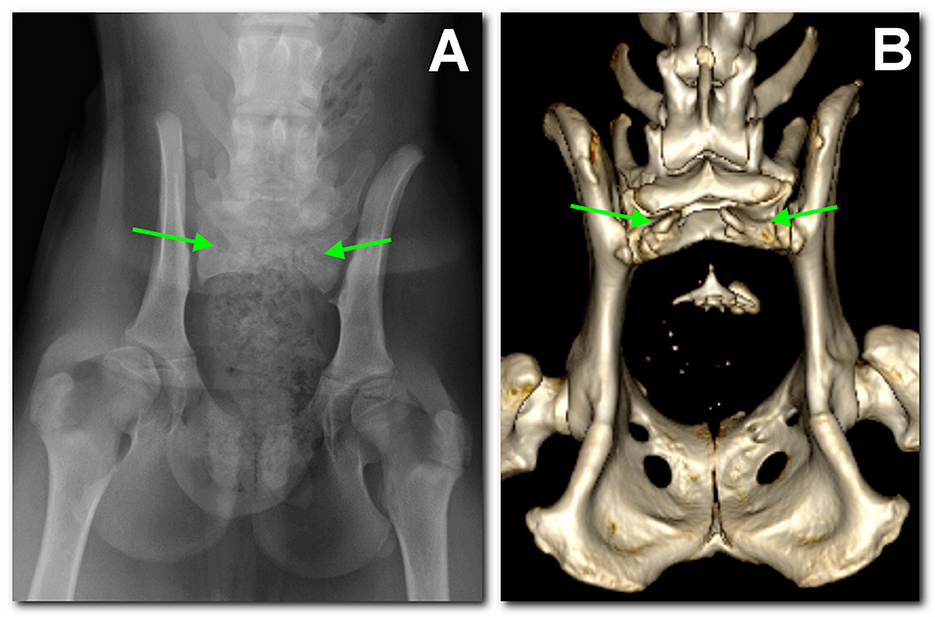

“Sacral agenesis in two boxer dogs …” from www.frontiersin.org and used with no modifications.